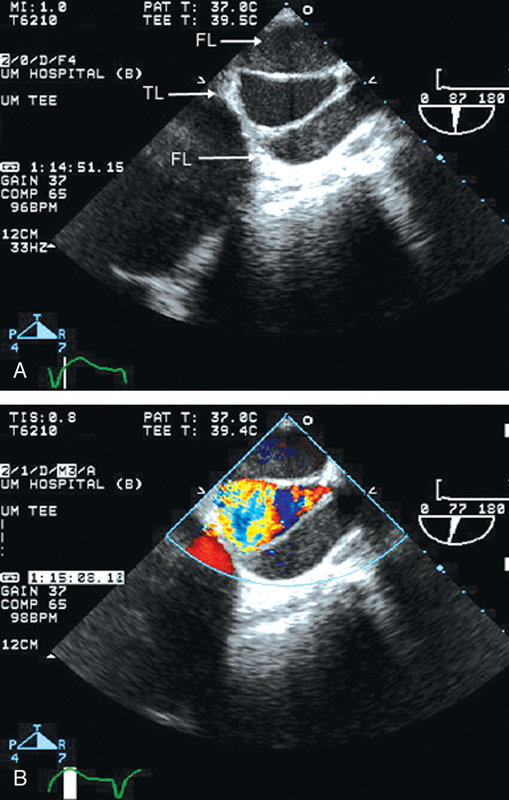

فحوصات تشخيصية لبعض امراض القلب والشرايين التاجية